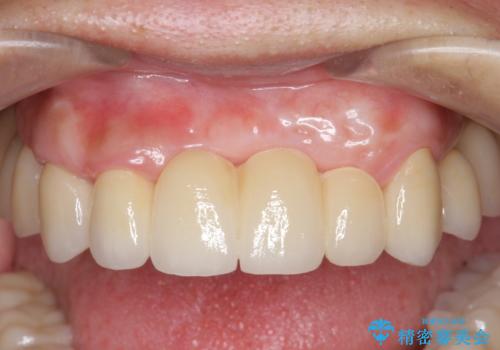

歯周病 全顎治療

- 前歯の見た目、入れ歯による噛めないことの改善を求めて来院されました。

検査により全顎的な歯周病治療、欠損のインプラント補綴、根管治療が必要な状態であることをお伝えし、治療を計画します。